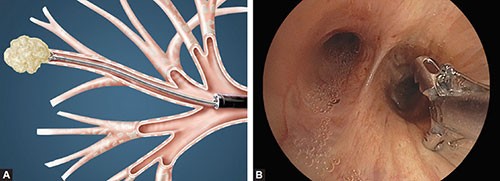

On bronchoscopy there was not seen any infiltration of airways.

Fibro-gastro-duodenoscopy showed superficial gastro-duodenitis.

Patient underwent again the endoscopic procedure where transbronchial biopsy was taken.

Figure 3. Endoscopic procedure where transbronchial biopsy was taken.

Histopathological result showed Mucinous lung adenocarcinoma.